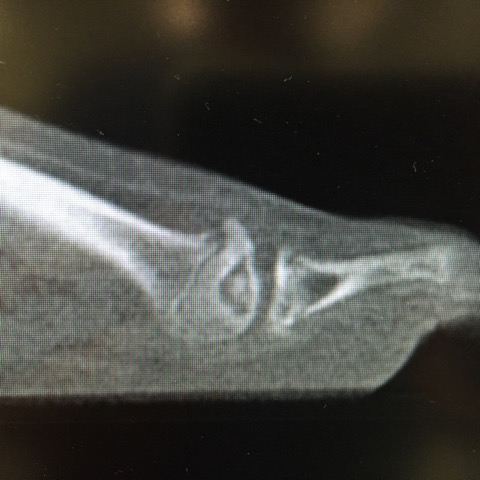

Previously, established classification systems did not usefully guide surgical treatment of Freiberg’s osteochondrosis. Smillie introduced what became the mainstay classification system for this condition in 1957.4 This description, based on radiographic findings, served as the historic framework on which surgeons could base treatment. However, this posed challenges, since radiographs alone do not reveal the full extent of the pathology in these types of cases.

Hoggett and colleagues described a new classification for Freiberg’s disease in a 2022 publication.3 They based their classification on thin-sliced computed tomography (CT) studies to evaluate the “zone” of the defect. The authors conducted a review of 24 CT scans over a 10-year period. They identified a sagittal imaging slice that displayed the widest portion of the proximal articular margins of the proximal phalanx and divided it anatomically into 2 articular zones—dorsal (zone 1) and plantar (zone 2). Eighteen patients that they studied had disease confined to zone 1, making them candidates for osteotomy, and 6 had pathology in both zones, which the authors deemed a more appropriate scenario for debridement.

A recently published February 2024 study elaborates further on this zone-based paradigm, reviewing 80 cases with CT images.5 These authors propose a 5-segment classification system and found excellent inter- and intra-observer agreement between evaluators in their study. However, this article will focus on the system outlined by Hoggett and team, as the 5-segment system necessitates more study on clinical and surgical applications.3